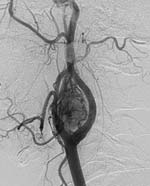

Консилиумом из двух специалистов по ангиографии устанавливался диагноз и оценивались источники кровоснабжения опухоли. Во всех случаях опухоль получала артериальное кровоснабжение из ветвей наружной сонной артерии. Характер кровоснабжения был множественный, но в 100% случаев основным питающим сосудом являлась восходящая глоточная артерия. Далее катетер продвигался в наружную сонную артерию и выполнялась селективная артериография последней. На снимках более детально визуализировалась опухоль, питающий сосуд, возможные коллатерали. Далее катетер продвигался в питающий опухоль сосуд, которым всегда, как правило, являлась упомянутая выше восходящая глоточная артерия (Рис. 2).

[Увеличить]

Рис. 2. Суперселективная артериография левой восходящей глоточной артерии. Опухоль целиком кровоснабжается из одного сосуда.